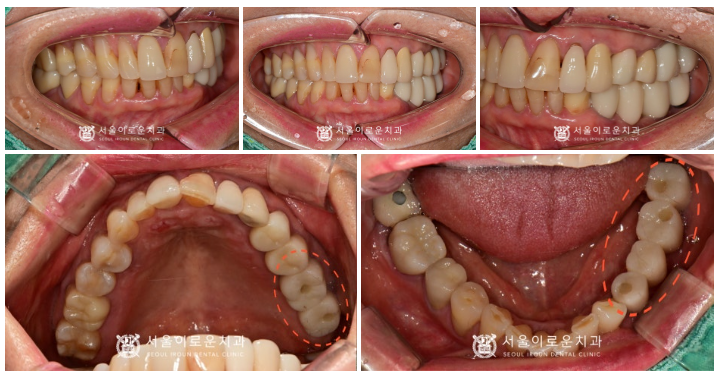

환.자분 구강 내 상황에 맞는

맞춤형 지대주인

custom abutment를 체결하여

자연치아와 강도가 가장 유사하고

심미적인 지르코니아 크라운으로

임플란트 보철을 마무리해 드렸습니다.

뼈이식을 병행한

임플란트 치료를

모두 마무리 한 구강 내 모습입니다.

환.자분께서는 이전에 흔들리고

씹.을 때 아팠던 상태가 사라져서

만.족해 하셨으며

아래턱 오른쪽 어금니 부위의 치료를

앞두고 있습니다.

✅ 전 > 후 ✅

(2024.01.26ㅡ>2024.07.29)